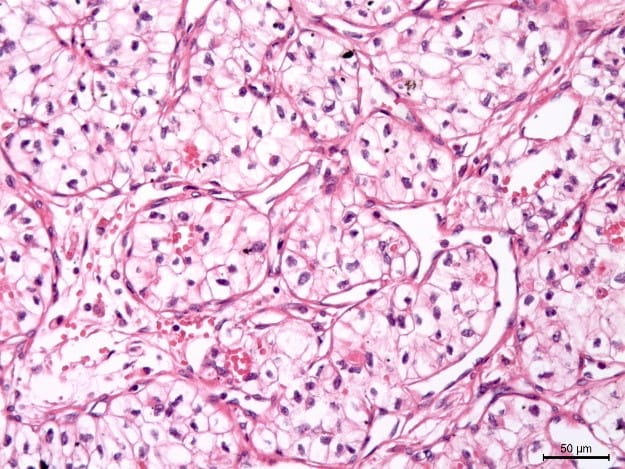

Histology and Histomorphometry

Founded by David Burr, PhD, and currently led by Lilian Plotkin, PhD, the Histology and Histomorphometry Core is currently active on the IU School of Medicine—Indianapolis campus as the Histology Lab Service Core and is currently being redesigned as it becomes a research core of the Indiana Center for Musculoskeletal Health.

The future design of the core will provide customized services to meet the needs of the musculoskeletal research community. This core will improve accessibility to, and reproducibility of, histological and histomorphometric analyses of all musculoskeletal tissues using standard (histology, immunohistochemistry) and newer (multi-photon microscopy, tissue clearing, 3D histology) techniques developed for musculoskeletal applications. The Histology and Histomorphometry Core will foster collaborations by providing services to musculoskeletal investigators who otherwise would not have access to them and facilitate multidisciplinary research by establishing new relationships with investigators outside the field who might have need for analysis of musculoskeletal tissues.